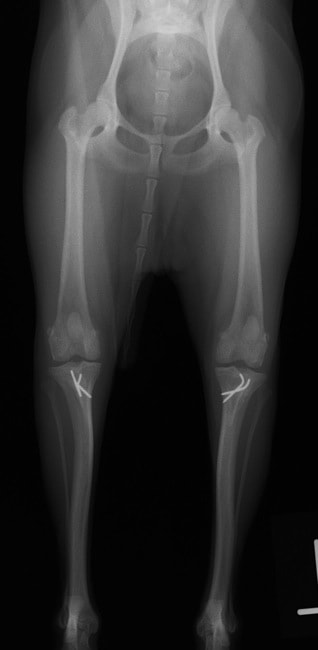

■ 症例22 ポメラニアン 1歳5か月 去勢雄

左後肢の挙上を主訴に来院した。整形学的検査、レントゲン検査より左右の膝蓋骨脱臼(左GradeⅡ〜Ⅲ、右Grade Ⅱ)を認めた。また、脛骨の前方引き出し試験の際に、引き出し兆候は認められないものの、疼痛が認められたため、前十字靭帯の損傷が疑われた。術中における、目視および関節内の操作によって、前十字靭帯の損傷や過伸展といった異常が認められなかったため、膝蓋骨脱臼の整復のみ実施した。手術手技は縫工筋及び内側広筋の解放、脛骨粗面の外側転位、滑車ブロック形造溝術、内外側関節包の縫縮を実施した。本症例は跛行もなく経過良好である。しかし、頸骨高平部の角度(TPA)が 右26.2°、左24.9°であり、解剖学的に前十字靭帯損傷のリスクが高いことから今後の経過に注意が必要である。